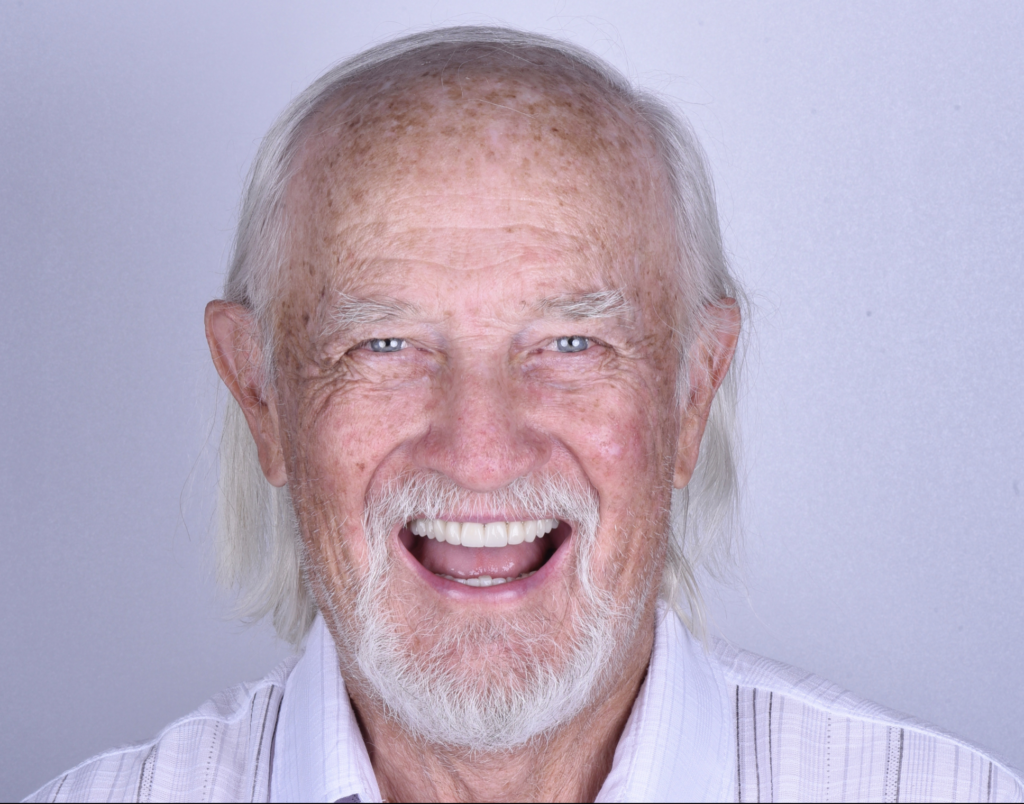

Una vez que recibí las restauraciones cerámicas, las probamos en la boca y procedimos a cementarlas. Después de aproximadamente dos meses, realizamos las fotos finales para el control de calidad, y el paciente estaba muy contento y satisfecho con su nueva sonrisa.

El Dr. Brunner ejemplifica la excelencia médica y lo recomendaría sin ningun

Desde mi primera cita, quedé cautivado por su dedicación en brindar una atención detallada y su enfoque incansable en encontrar la solución óptima para mi situación médica. El Dr. Brunner ejemplifica la excelencia médica y lo recomendaría sin ninguna duda a cualquier persona que busque recibir una atención de calidad sin igual.